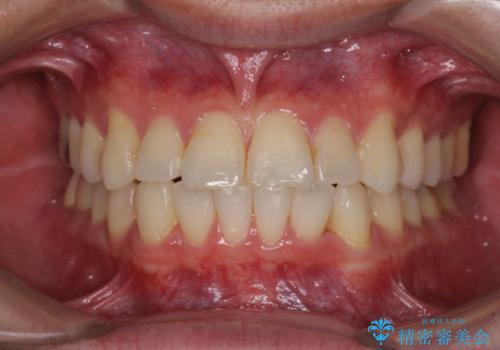

全体のガタガタをインビザラインできれいな歯並びへ